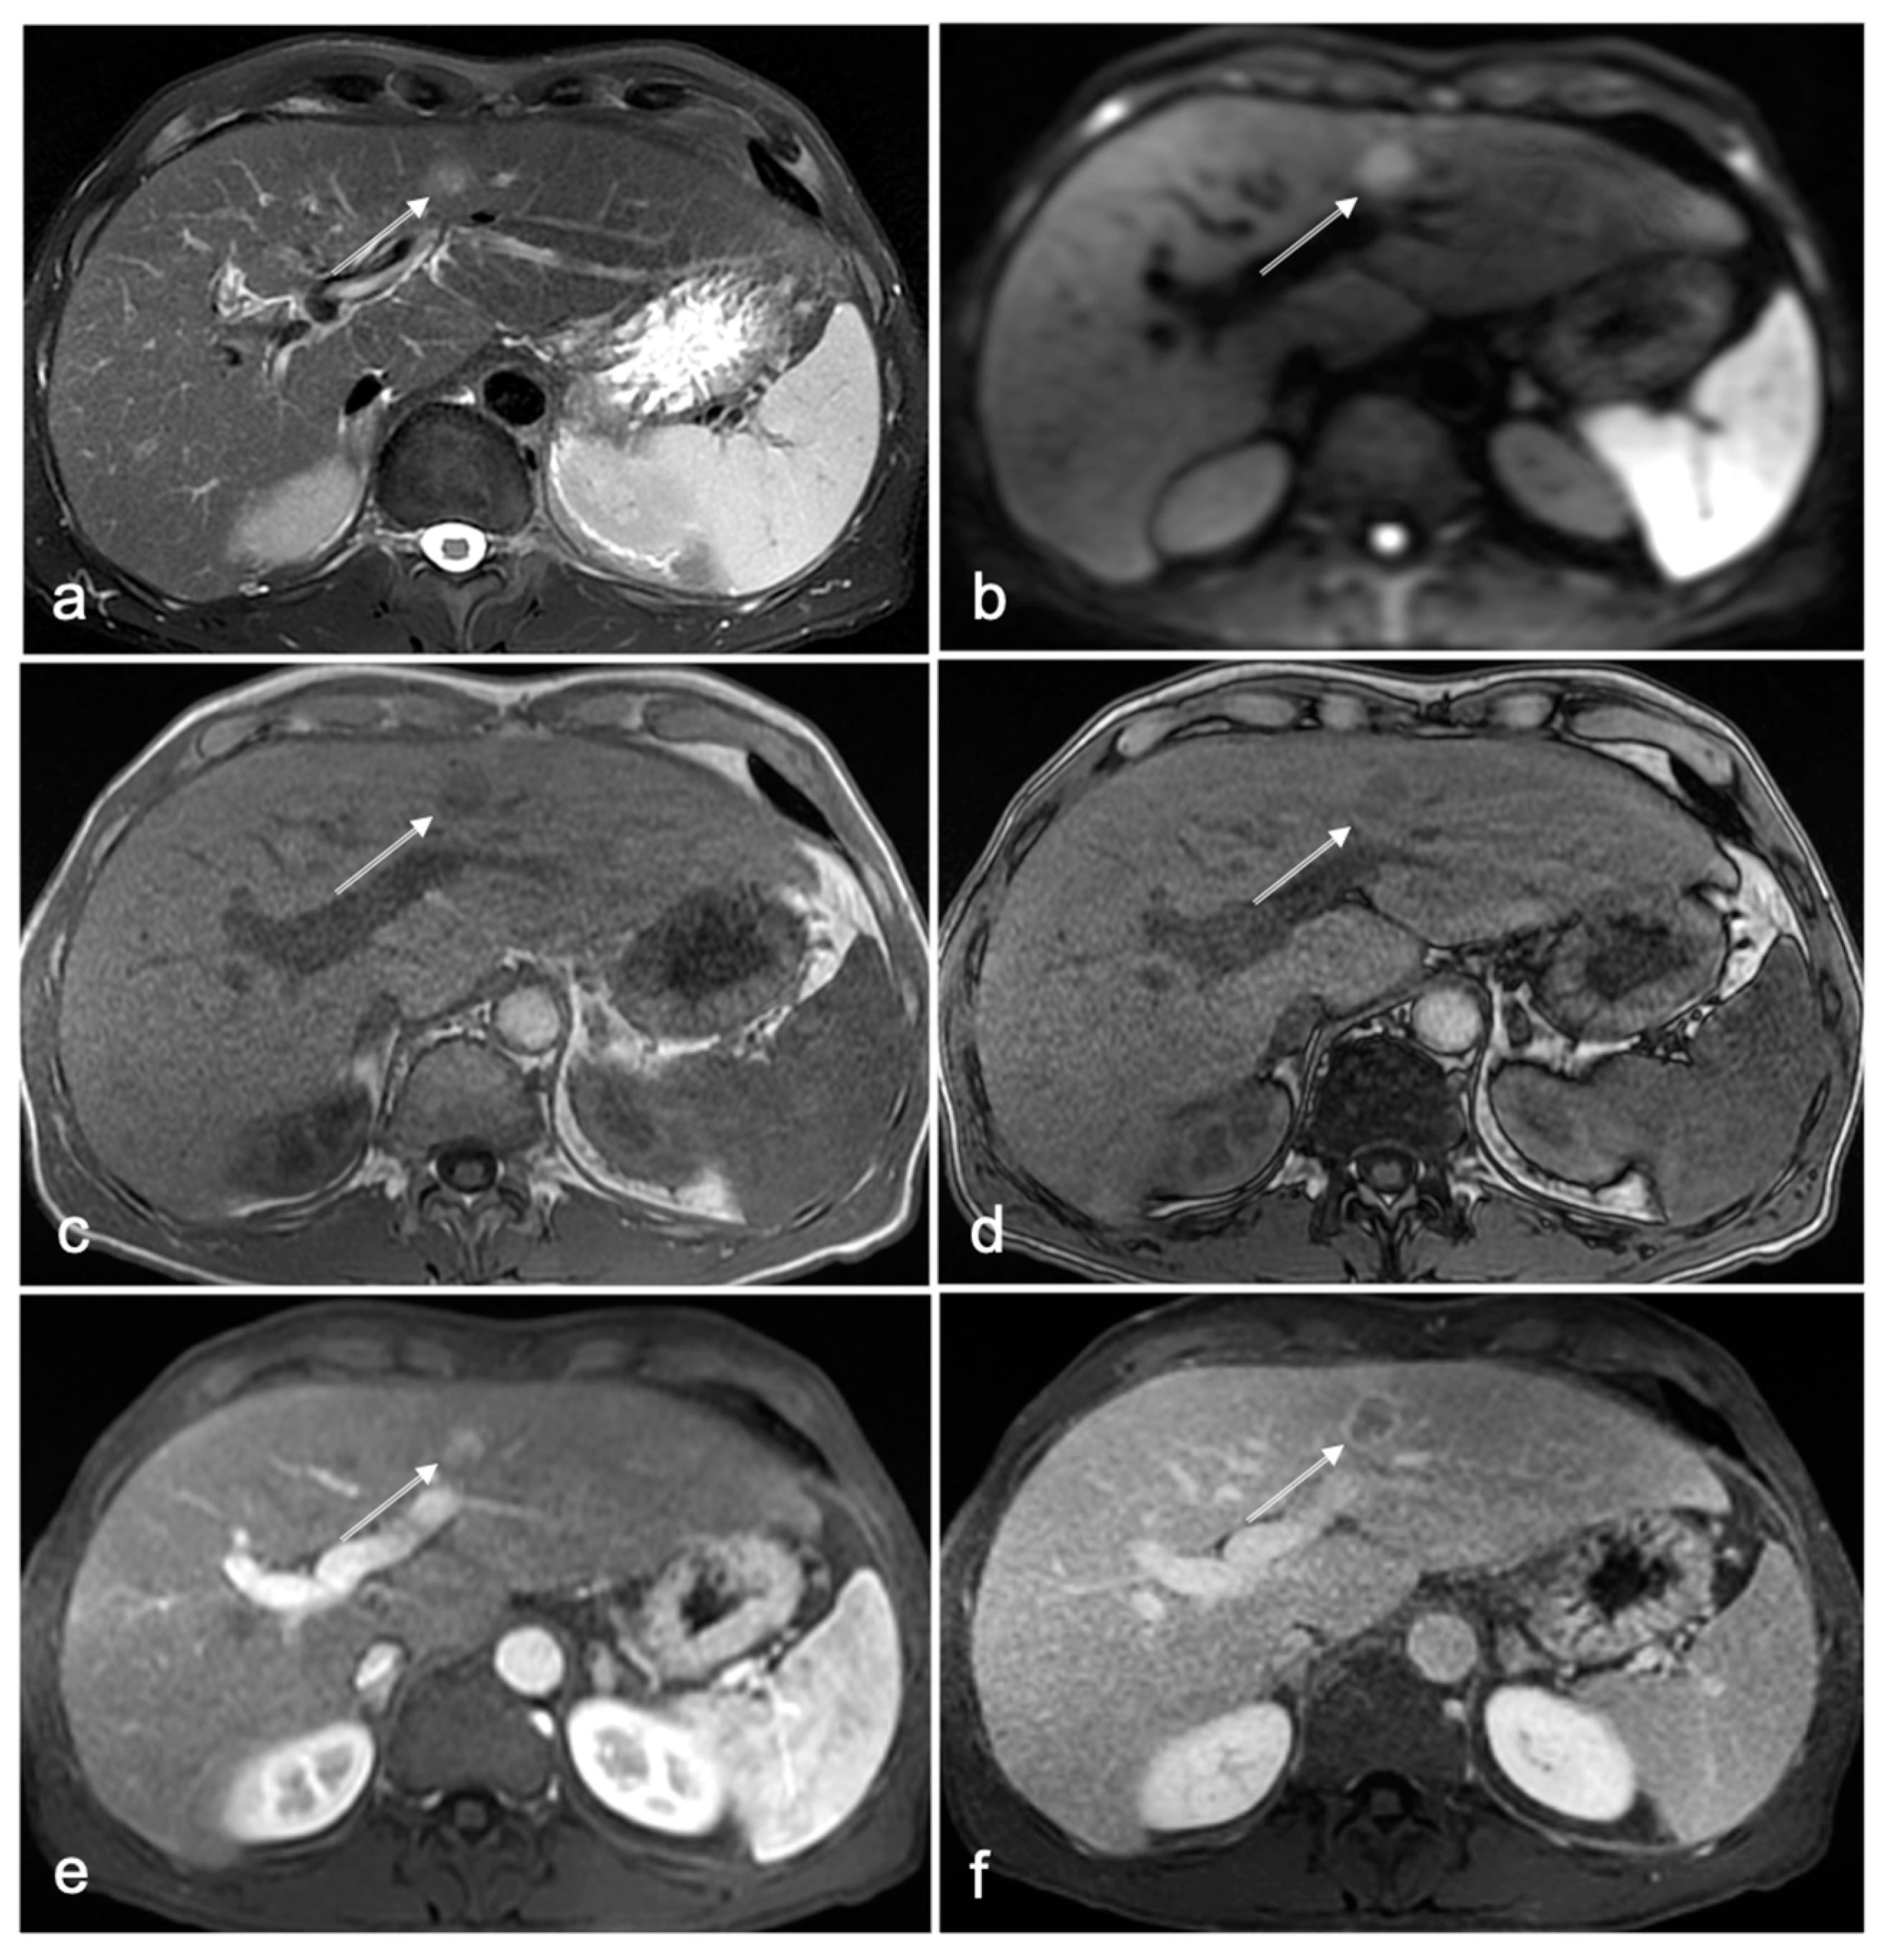

Figure 2.

Fifty-two-year-old male patient with liver cirrhosis owing to chronic hepatitis C infection. NC-AMRI (a–d) demonstrates a small lesion (arrow (a–f)) in segment 4 that is hyperintense on axial T2W FS (a) and DWI (b), and hypointense on T1W in-phase (c) and opposed-phase (d) imaging, without signs of intracellular fat. CE-MRI (e,f) shows hyperenhancement in the arterial phase (e) with washout (arrow) in the delayed phase and capsular enhancement (f), confirming an HCC lesion (Li-RADS 5 lesion). The lesion was treated with radiofrequency ablation.